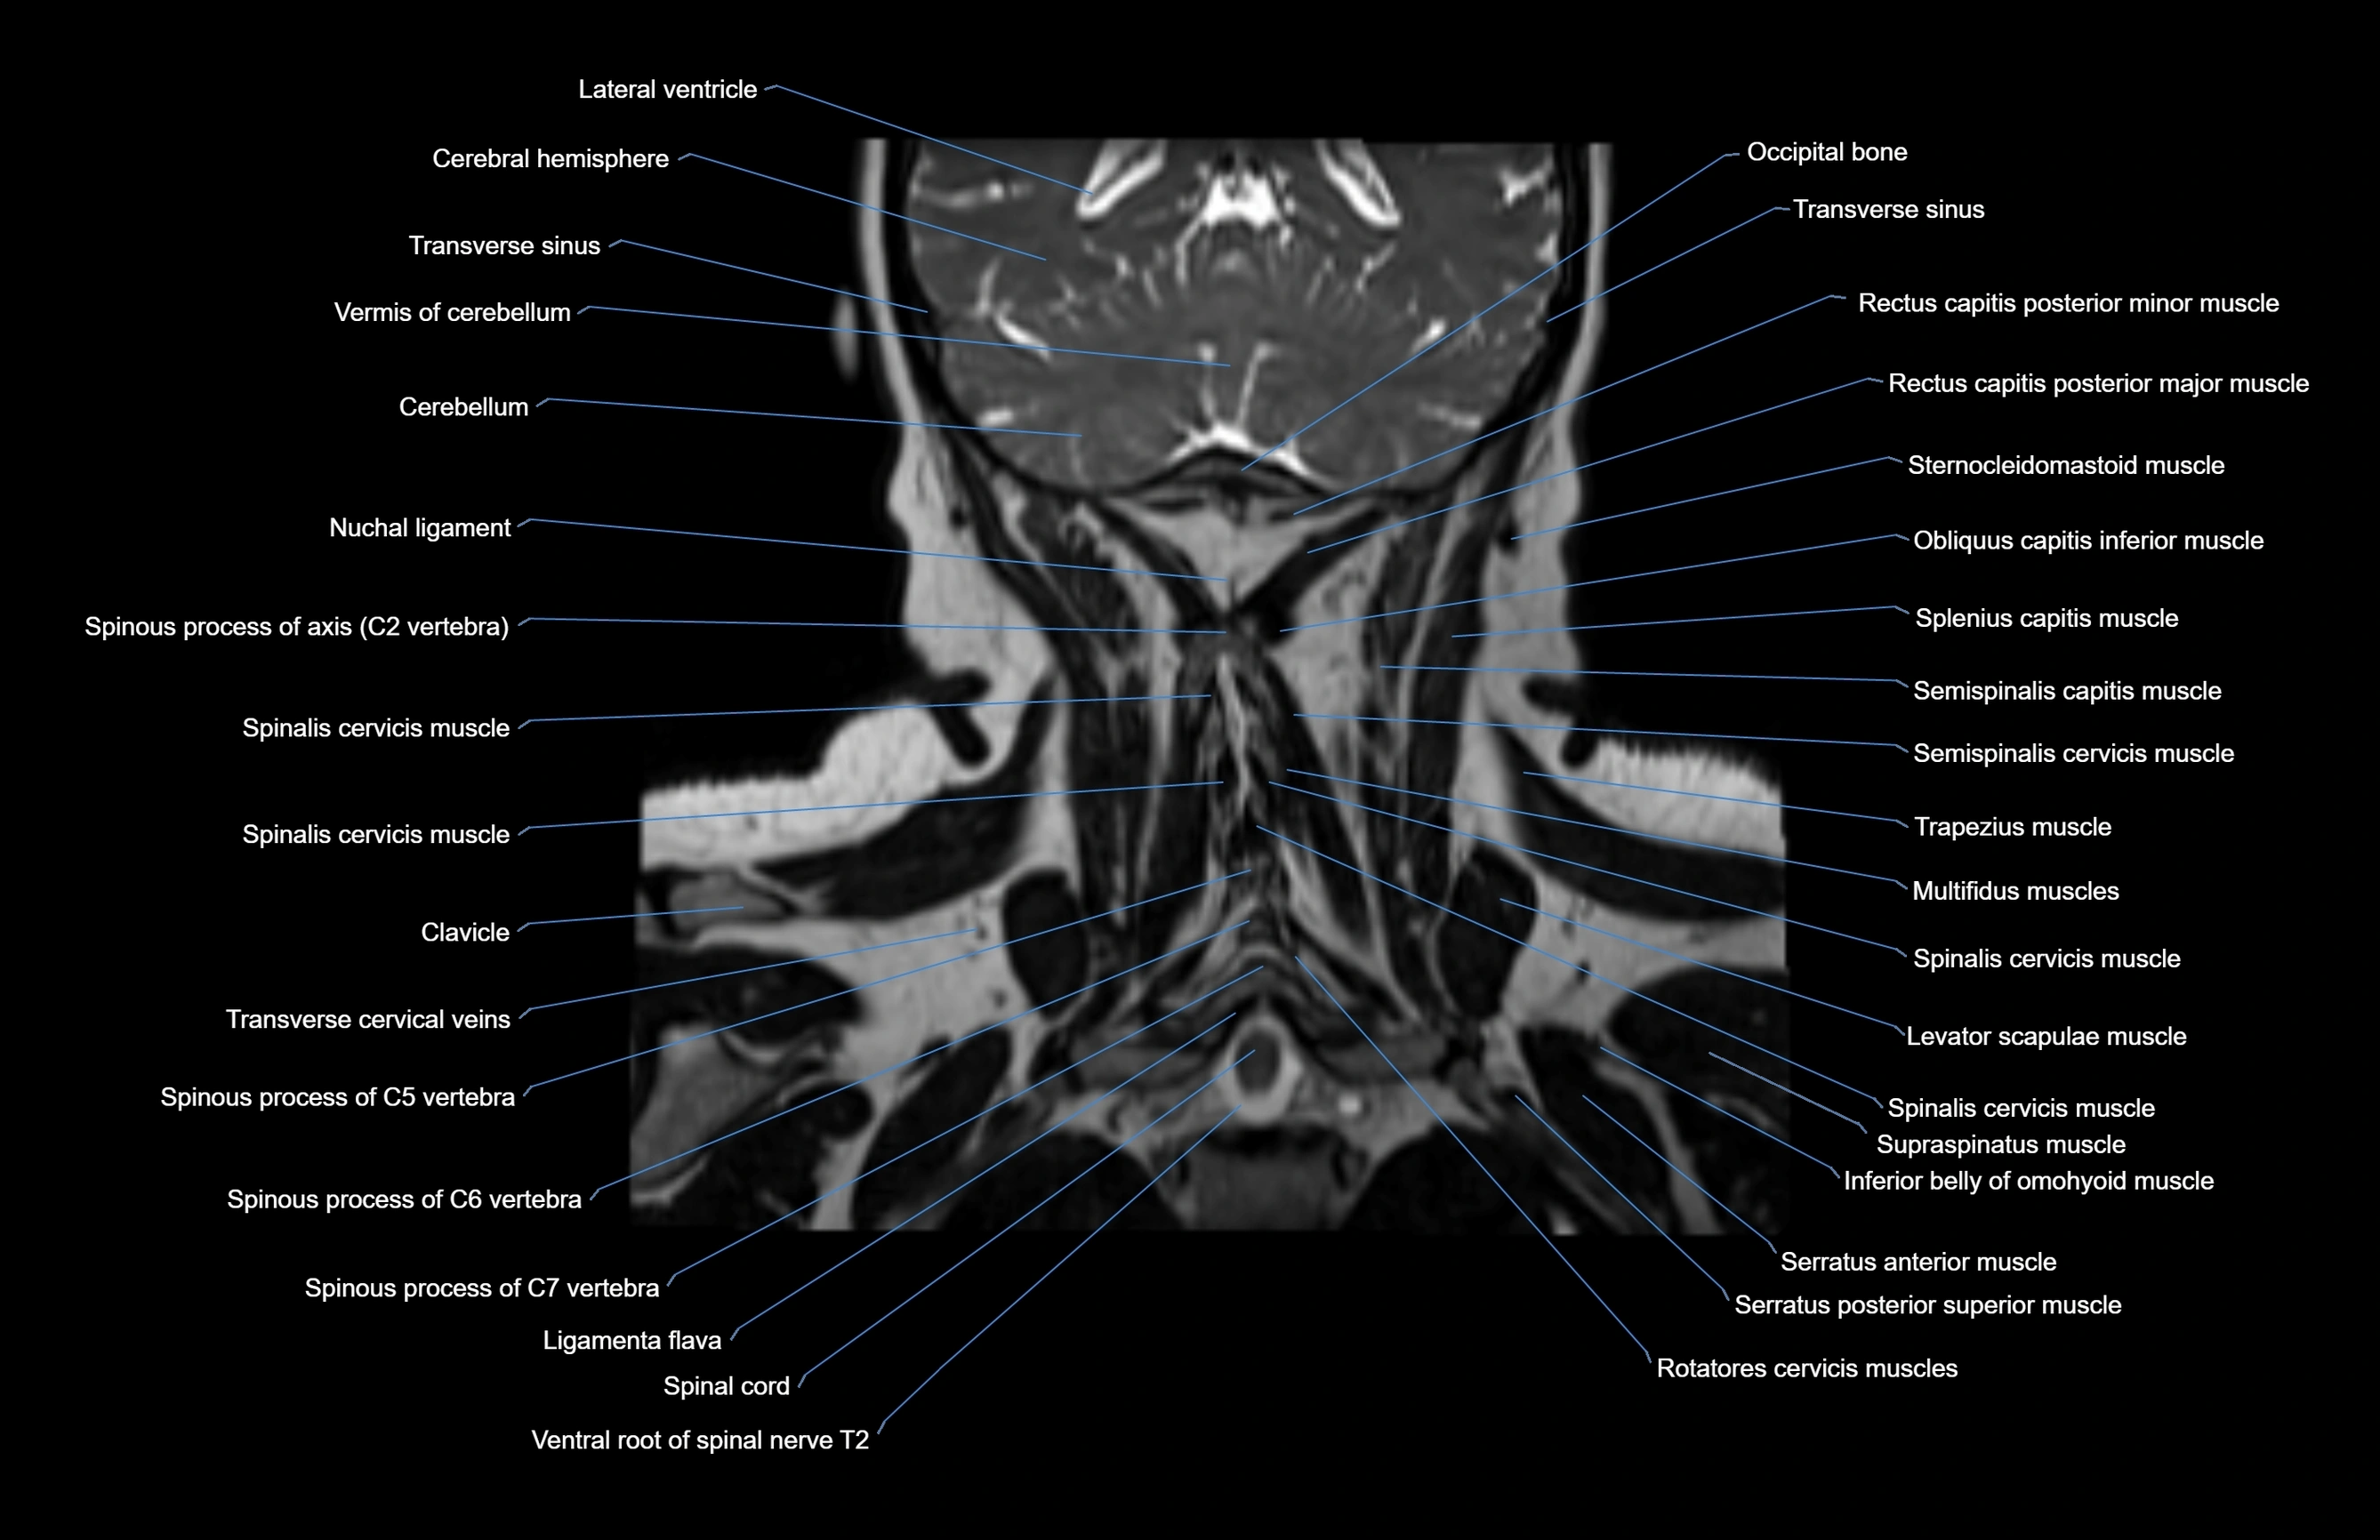

MRI images